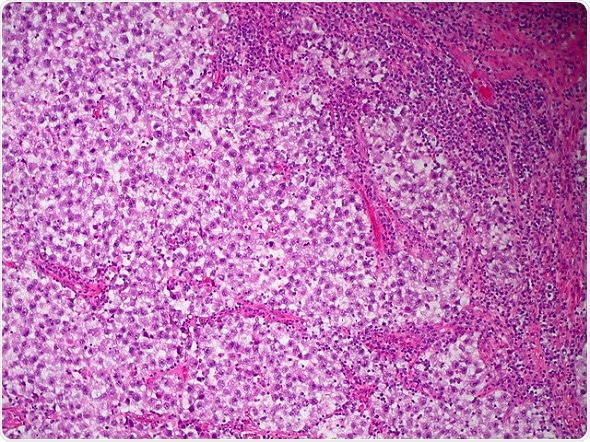

Credit: Ed Uthman, Flickr